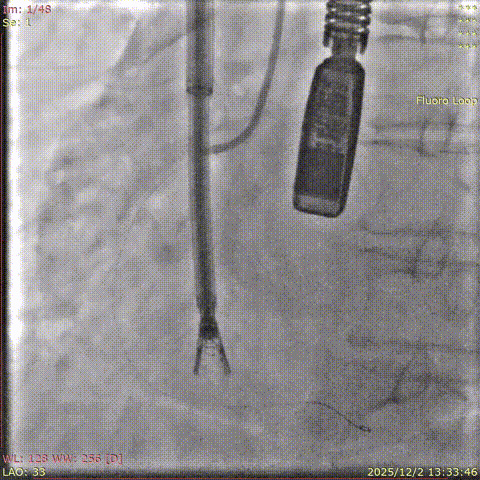

CT : The tricuspid annulus has a circumference of 139 mm and an area of 1423 mm². The overall distance between the RCA and TA was greater than 3 mm in both systole and diastole. The right coronary artery is slightly deviated toward the atrial side, indicating a low risk of coronary artery injury during the procedure.

Baseline coronary angiography

Post-closure angiography confirmed that the right coronary artery was not affected.

Coronary angiography after the deployment of the second clip.